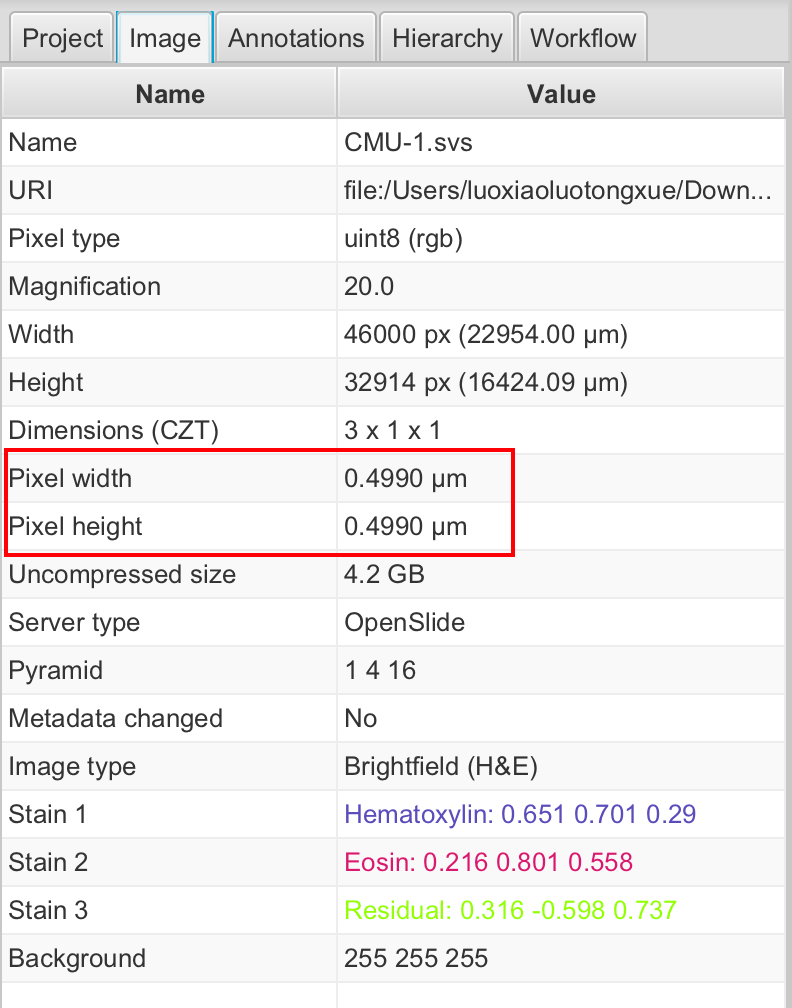

1-4:设置像素大小

如果存储在图像文件中,QuPath 应自动获取像素大小并将其显示在**“图像”**选项卡(“像素宽度”和“像素高度”)下。

如果没有,您可以通过双击任一行并输入正确的值来手动设置像素大小。